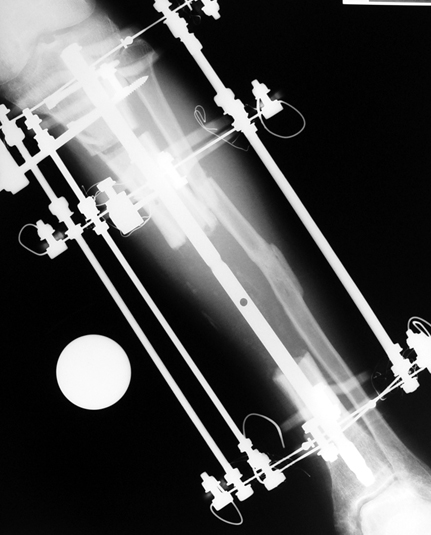

Uygun radikal debridman tüm nekrotik kemik ve yumuşak dokuların çıkartılmasını gerektirir, ve sıklıkla uzuvda instabiliteye neden olur. Kalan kemik ve yumuşak doku defektinin bir şekilde fiksasyonu ve rekonstrüksiyonu gereklidir. İlizarov’un ortaya koyduğu distraksiyon osteogenezi yöntemi, kaynamanın elde edilmesi, deformitenin düzeltilmesi, bacak boy eşitsizliğinin giderilmesi ve segmental defektlerin rekonstrükte edilmesi için başarıyla kullanılmaktadır.

Eksternal fiksatör ile geçen süre (eksternal fiksasyon indeksi), gereken distraksiyon miktarına bağlıdır ve bu süre boyunca bazı komplikasyonlarla karşılaşılabilir. Distraksiyon dönemi sona erdikten sonra, distraksiyon süresinin iki katını aşan konsolidasyon döneminde hastalar eksternal fiksatörü zorlukla tolere edebilirler. Yeterli konsolidasyon sağlanmadan eksternal fiksatör çıkartılırsa ise kırıklar, deformite ve kısalık oluşabilir. Hastanın fiksatör ile birlikte geçirdiği sürenin azaltılması ve böylece hasta konforunun ve aktivite düzeyinin arttırılması için intramedüller çivi üzerinden uzatma yöntemi uygulanmaktadır. Bu yöntemde distraksiyon dönemi sona erdiğinde kemiğin içindeki çivi statik olarak kilitlenmekte ve eksternal fiksatör çıkartılmaktadır. Stabilizasyon intramedüller çivi tarafından sağlandıktan sonra konsolidasyon dönemi gerçekleşmektedir. Bu şekilde hem eksternal fiksatörün uzun süre kalmasından hem de erken çıkartılmasından kaynaklanan komplikasyonların önüne geçilmektedir.